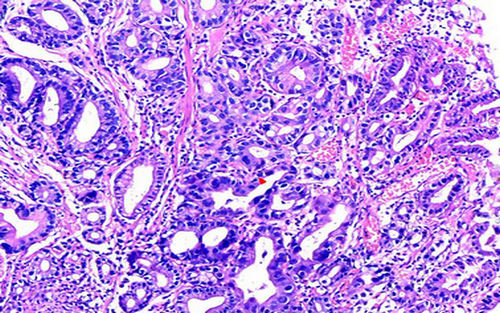

小土豆跟着农人老师学本领-直肠活检 乳头状结构 乳头的轴心为腺窝脉管组织 不规则的腺管浸润性生长 绒毛管状腺瘤局部癌变